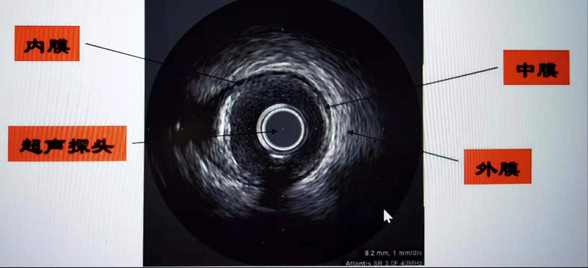

众所周知,心脏、腹部可以做超声检查,血管内超声(Intra Vascular UltraSound,IVUS)技术,简单通俗地说,就是在心脏血管内做超声检查,将微型化的超声探头通过导管的技术送入血管腔内,从而提供管壁在内的横截面图像。精细程度堪称心血管介入术中医生的“火眼金睛”。

血管内超声(intravenous ultrasound,IVUS)是指无创性的超声技术和有创性的导管技术相结合,使用末端连接有超声探针的特殊导管进行的医学成像技术。血管内超声是通过心导管将微型化的超声换能器置入心血管腔内,显示心血管断面形态和(或)血流图形,主要包括超声显像技术和多普勒血流测定两方面。这种技术使得超声技术,如压电传导或者超声传感器得以用于检查血管内壁的情况。